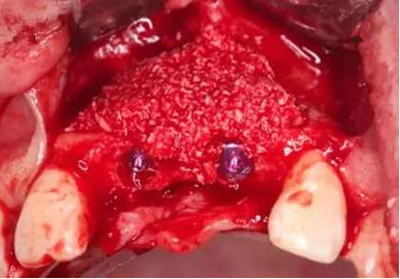

種植體頰側(cè)骨缺損處植入Bio-Oss骨替代品

覆蓋雙層Bio-Gide膠原膜